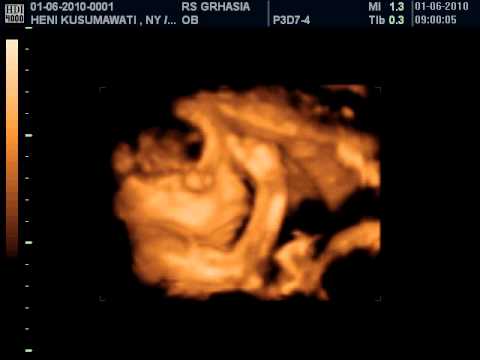

Gambar Janin 25 Minggu